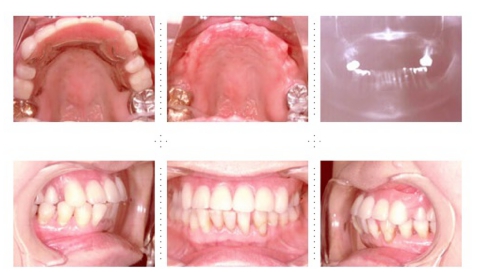

症例2

62才 女性

上顎は総義歯、下顎はブリッジと局部床義歯が装着。義歯は違和感があり、食事も不便を感じ、審美的にも人前にでるのが苦痛に感じていました。この状態を打破するためにも、「インプラント治療に自分の人生を賭けてみたい」という覚悟で来院されました。インプラント手術に対する恐怖心も強くお持ちでした。このような骨幅が狭いケースでは、X線撮影と共にCT撮影による画像診断とインプラント埋入シミュレーションが重要です。

下顎は両側犬歯を残し、他は抜歯。インプラント7本埋入。 上顎はインプラント8本埋入。 インプラント手術を受けられる患者さんは、前の晩眠れない程の不安感、恐怖心を持って来院されます。実際には麻酔注射は痛みを感じず、インプラント手術も痛みも無く、短時間(1本平均3分)で終わるという、当院独自のテクニックにより、2回目からのインプラント手術は気楽になるようです。 前歯は仮歯の段階で患者さん、歯科医、技工士の三者で、審美性・機能性の面から10回以上形態修正を繰り返し検討した後、上・下顎共に前歯・小臼歯はセラミック(MB)クラウン、大臼歯はゴールドクラウンを装着。ご本人とご家族の方にも、「アンチエイジングには、審美インプラント治療が一番効果あり」と大変喜んで頂きました。